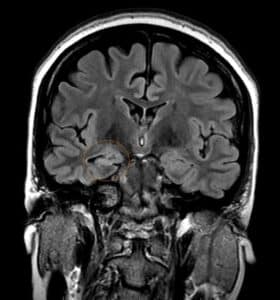

Temporal lobe epilepsy is the most common form of focal epilepsy. 70% of temporal lobe epilepsies arise from mesial temporal sclerosis/hippocampal sclerosis (Figure 4), which involves neuronal cell loss, gliosis, and sclerosis primarily in the dentate gyrus and CA1 section of the hippocampus, and loss of hippocampal volume and an increased T2 signal on MRI. Other causes of temporal lobe epilepsy include encephalitis (e.g., herpes simplex encephalitis), developmental disorders, neurodegenerative disorders, and tumors. Seizures occur in clusters lasting 30 seconds to 2 minutes on average. Typical symptoms include a visceral, olfactory, or auditory aura or feelings of familiarity or unfamiliarity, ictal motor symptoms –classically oral alimentary automatisms, or autonomic symptoms, and altered mental state without total loss of consciousness. With recurrent seizures, the limbic system can become impaired, resulting in impairment of libido, the menstrual cycle, and fertility, and memory. EEG shows temporal lobe spikes, and treatment includes pharmacotherapy, but due to the overall unfavorable prognosis of this syndrome, surgical options are offered for medication-resistant cases (22).

Figure 4: Right mesial temporal sclerosis